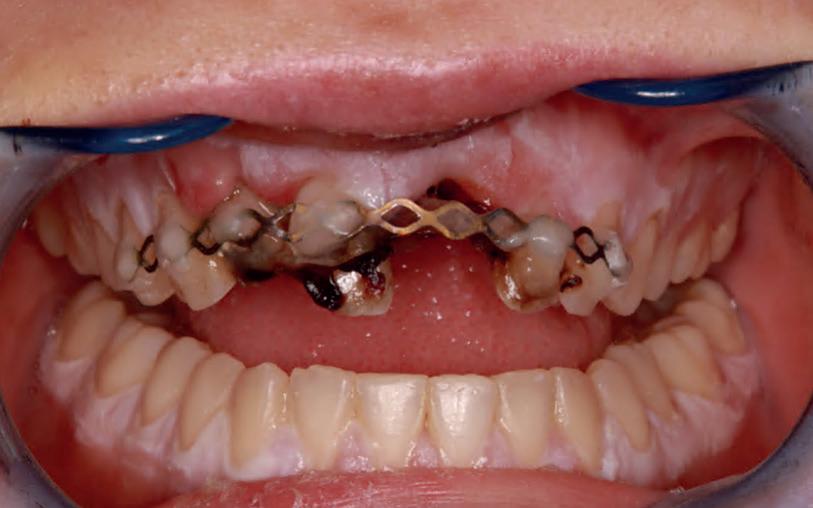

Een week later zie ik de jongedame samen met haar moeder voor een uitgebreid consult en maak ik lichtfoto’s. Deze zijn altijd erg waardevol in dit soort trauma casussen (foto 9).

Meteen na het ongeval is gecontroleerd of de patiënt nog beschermd was tegen tetanus. Ik bespreek de ontstane gebitssituatie; een tot voor kort volledige gave dentitie. Nu een 11 met een horizontale wortelfractuur en een gereplanteerde 21 met een necrotische pulpa. De pulpa van element 11 reageert positief op de koudetest. Uiteraard wordt er een afwachtend beleid in gesteld.

Gelukkig zijn de patiënt en haar moeder erg nuchter en begrijpen de situatie volkomen. In dezelfde afspraak wordt er gestart met een endodontische behandeling van element 21. Plaats hierbij geen cofferdamklem op het element zelf. Deze staat nog niet vast genoeg.

9. Situatie één week na het trauma.

10-11. Vier weken na het trauma is de TTS verwijderd en de endodontische behandeling aan element 11 voltooid. Vanwege de brede apicale diameter is er afgesloten met MTA).